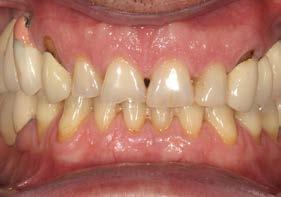

Explantación atraumática y recambio de implantes mal posicionados y afectados por periimplantitis sumado a la utilización de implantes estrechos y cortos. Enfoque mínimamente invasivo de un caso de atrofia ósea moderada

42 | INVESTIGACIÓN CLÍNICA